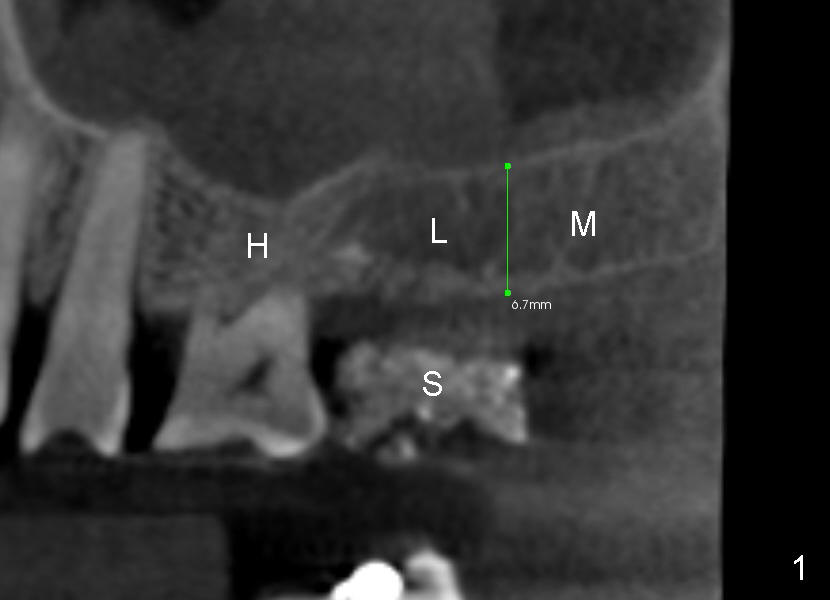

Davis is 53 years old.  This Wednesday an implant will be placed at the site of #2.  Since the case is complicated (involving multiple implant restoration), CT scan stent is fabricated using Calcium Sulphate (Fig.1 (sagittal section) S).  The stent helps treatment planning: placing 6x11 mm gingiva-level tapered implant in the most ideal restorative position (Fig.3,4 (coronal section)).  Since bone height is less than 7 mm (Fig.1), sinus lift is planned (Fig.3,4).

The method of sinus lift depends upon bone density.  A brief look at the CT scan reveals that bonedensity is high (H, Fig.1) in the dentulous area  (1st molar), medium (M) in the tuberosity and low (L) in the edentulous area (2nd molar).  The lower right of every CT planar image shows Hounsfield unit of a particular area where the mouse curse rests.  The map of bone density is shown in Fig.2.